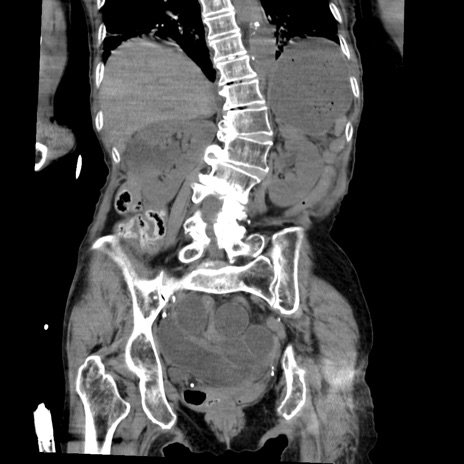

症例27(冠状断像)

【症例】80歳代女性

【主訴】嘔吐、腹痛

【現病歴】数時間前より嘔吐あり。心窩部痛出現し、徐々に右下腹痛あり。その後も数回嘔吐あり救急搬送となる。

【既往歴】左大腿骨頚部骨折手術

【身体所見】腹部は膨隆しているが軟らかく圧痛なし。腸雑音はやや亢進。

【データ】WBC 12000、CRP 19.05